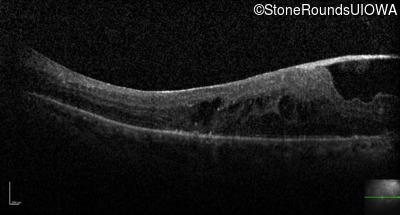

Optical Coherence Tomography - Left - 20/160

Exemplar / OCT Stack